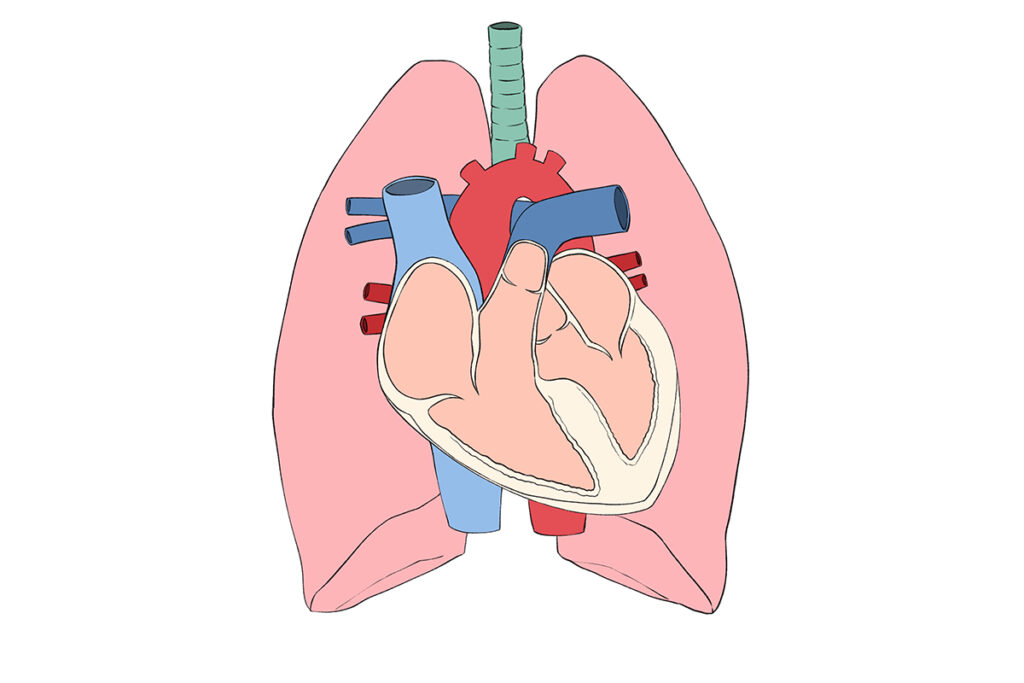

わんちゃんの⼼臓は、右⼼房/右⼼室・左⼼房/左⼼室という4つの部屋からできていま

す。それぞれの間には⾎液が逆流しないように「弁」があります。そのうち、左⼼房と

左⼼室を隔てているのが「僧帽弁」です。